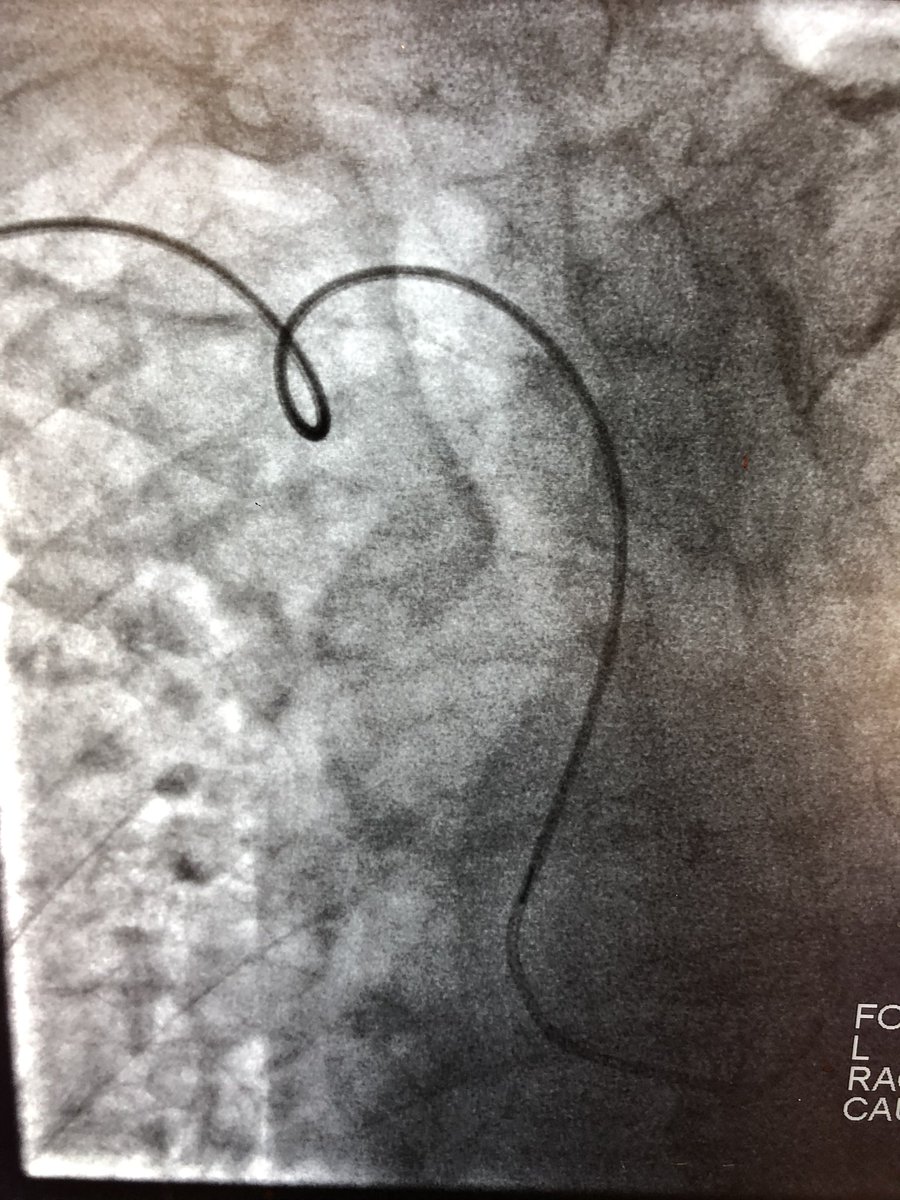

Ok, if we now have the BATMAN (Balloon-Assisted Translocation of the Anterior Mitral Valve) and ROBIN (Retrograde Radiofrequency Balloon-Assisted Optimization of Neo-LVOT) techniques, I’ll raise the stakes with: